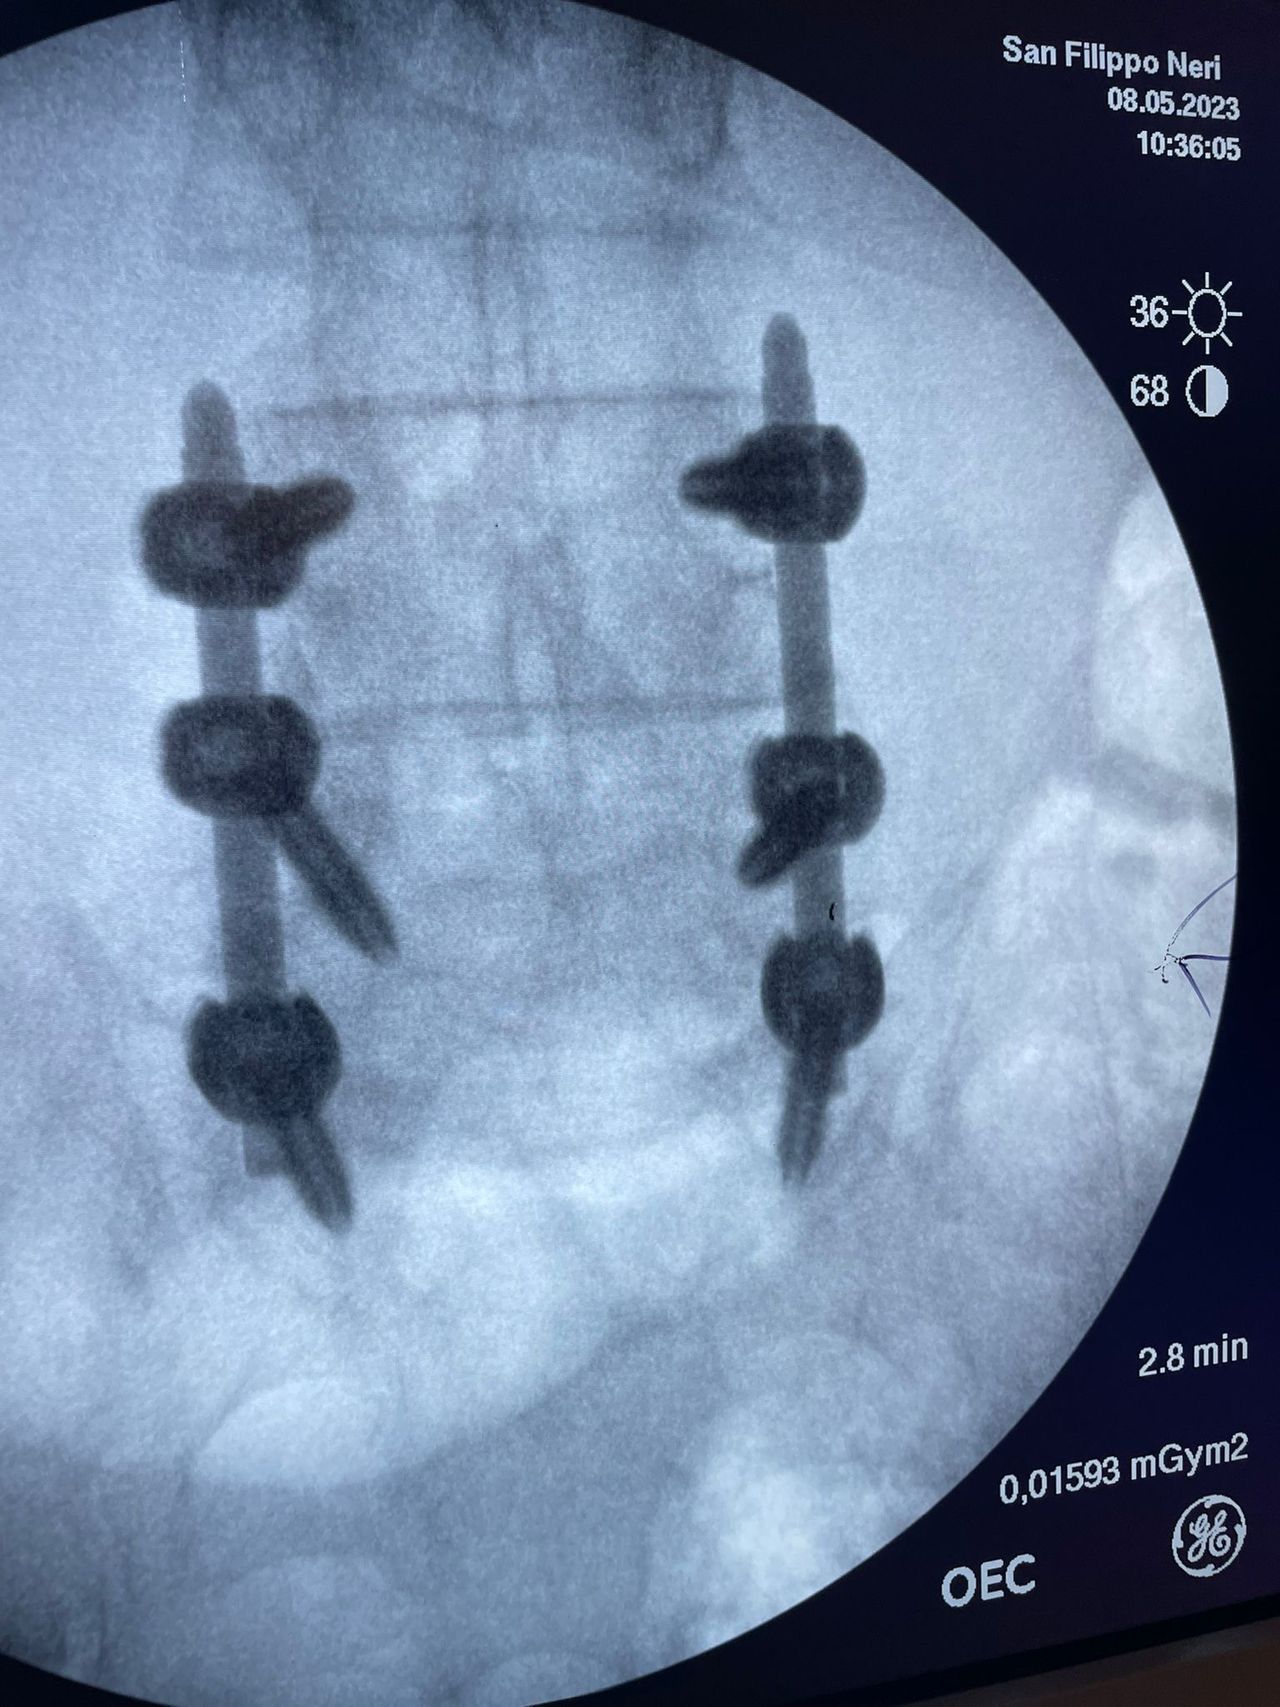

- Chirurgia Mininvasiva percutanea vertebrale - stabilizzazioni e artrodesi intersomatiche (per fratture vertebrali, spondilolistesi, instabilità vertebrali, discopatie)

- RX scopia intraoperatoria